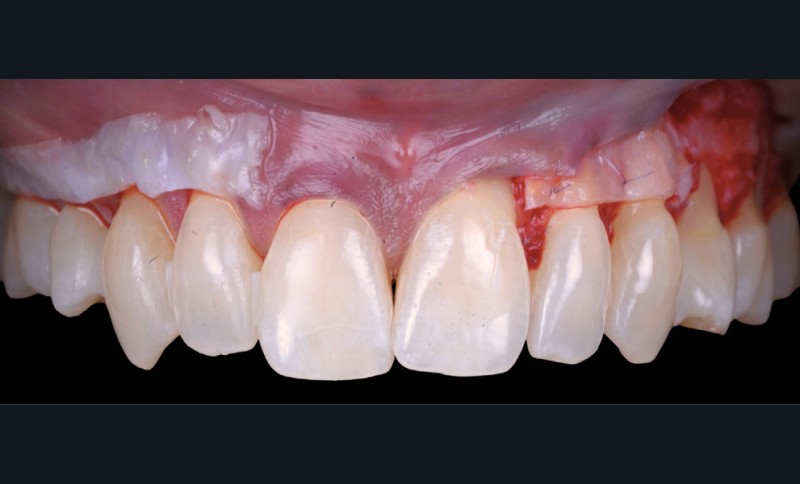

Le choix de la technique est guidé par un arbre décisionnel [4] prenant en compte le nombre de récessions, la quantité de tissu kératinisé et plusieurs points clés. Ici, ce sont les papilles qui vont guider notre décision :

- secteur 1 : papilles étroites et rétruses (fig. 2) ➠ technique de tunnellisation ;